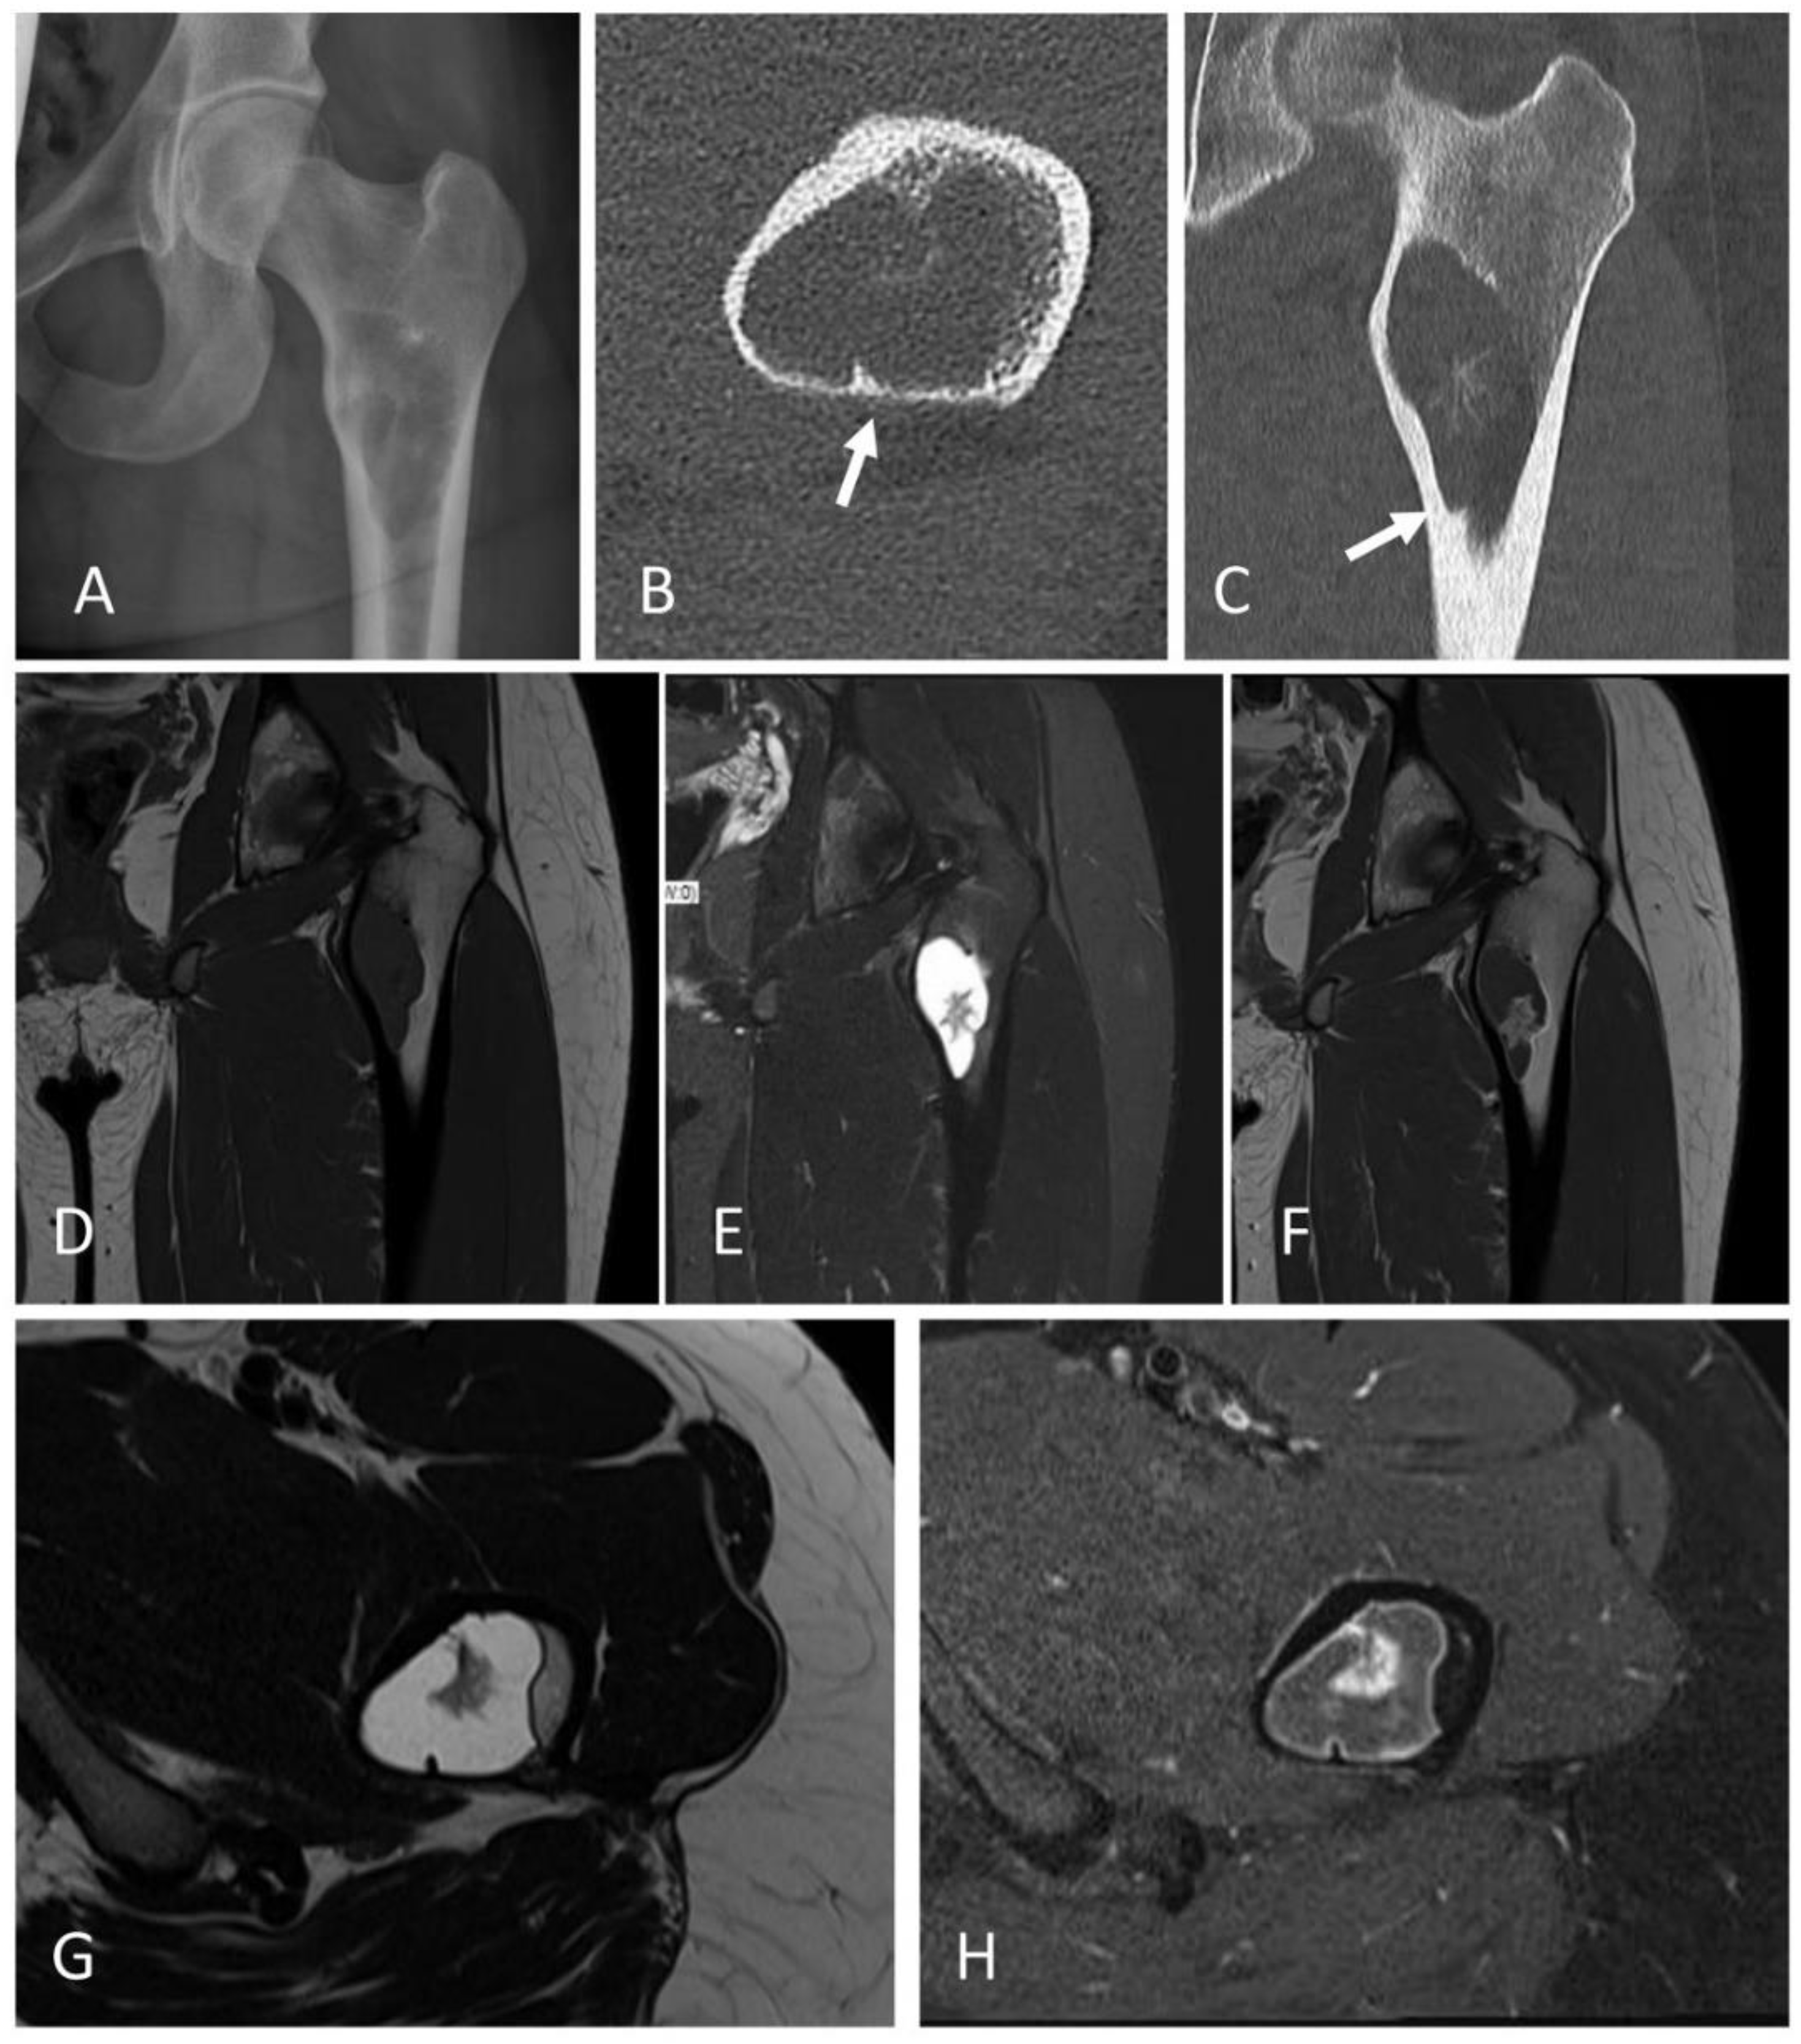

2.2. Complex Cystic Bone Lesions (Cases #2 & 3)

2.4. EWSR1::NFATC2-Rearranged Bone Sarcoma (Case #5)